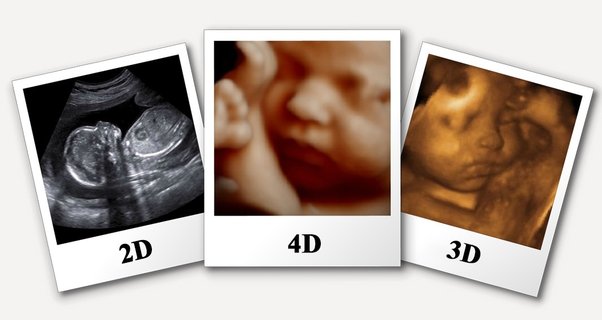

Jenis-jenis USG Fetomaternal

Jenis-jenis USG Fetomaternal | Sumber: eHealth Community

Pemeriksaan ini tidak hanya terbatas pada satu teknologi, melainkan menggunakan kombinasi berbagai jenis USG untuk mendapatkan gambaran kesehatan janin yang paling lengkap dan akurat.

2. USG 3D/4D

Ilustrasi USG 3D/4D | Sumber: Lux Radiology

Jika USG 2D memberikan "potongan" organ, maka USG 3D menyatukan potongan-potongan tersebut menjadi gambar statis tiga dimensi yang jelas.

Sementara itu, USG 4D menambahkan elemen waktu, menghasilkan video real-time yang memungkinkan Anda melihat janin bergerak, menguap, atau mengisap jari.

- Identifikasi anomali permukaan: USG ini sangat efektif untuk mendeteksi kelainan struktural pada permukaan tubuh janin, seperti bibir sumbing (sumbing palatum), kelainan bentuk hidung, atau deformitas pada anggota gerak.

- Korelasi klinis: Gambar-gambar ini sering kali membantu orang tua dan dokter memahami kondisi janin secara visual, yang sangat membantu dalam perencanaan intervensi setelah kelahiran.